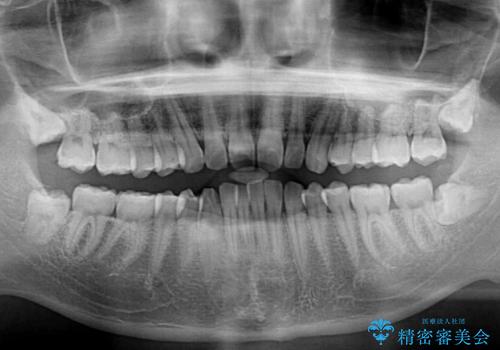

- 上下前歯のデコボコと下の前歯が隠れるほどの深い咬み合わせを気にして来院された患者様です。

インビザラインによる上下歯列の拡大と、IPR(歯と歯の間を削る)にるスペースの獲得により、口元のデコボコとディープバイトを改善することとしました。